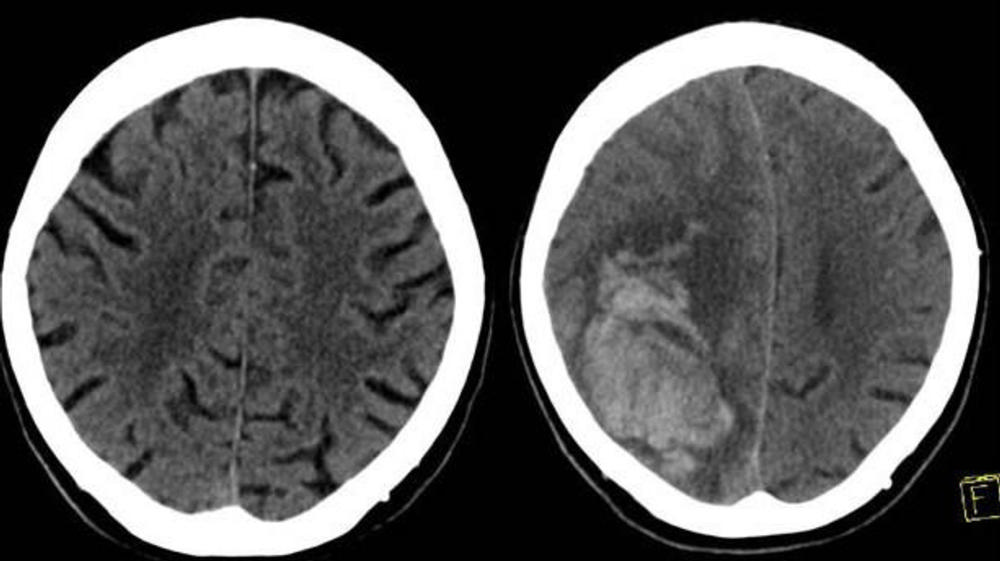

Figure 1. The left image shows the initial CT scan of the brain in a patient on both clopidogrel (Plavix) and aspirin who presented to the Emergency Department with head trauma that did not demonstrate any intracranial hemorrhage. The right image shows a head CT obtained 24 hours later demonstrating a large parenchymal hemorrhage in the right frontal/parietal region. The patient died shortly after the second examination.